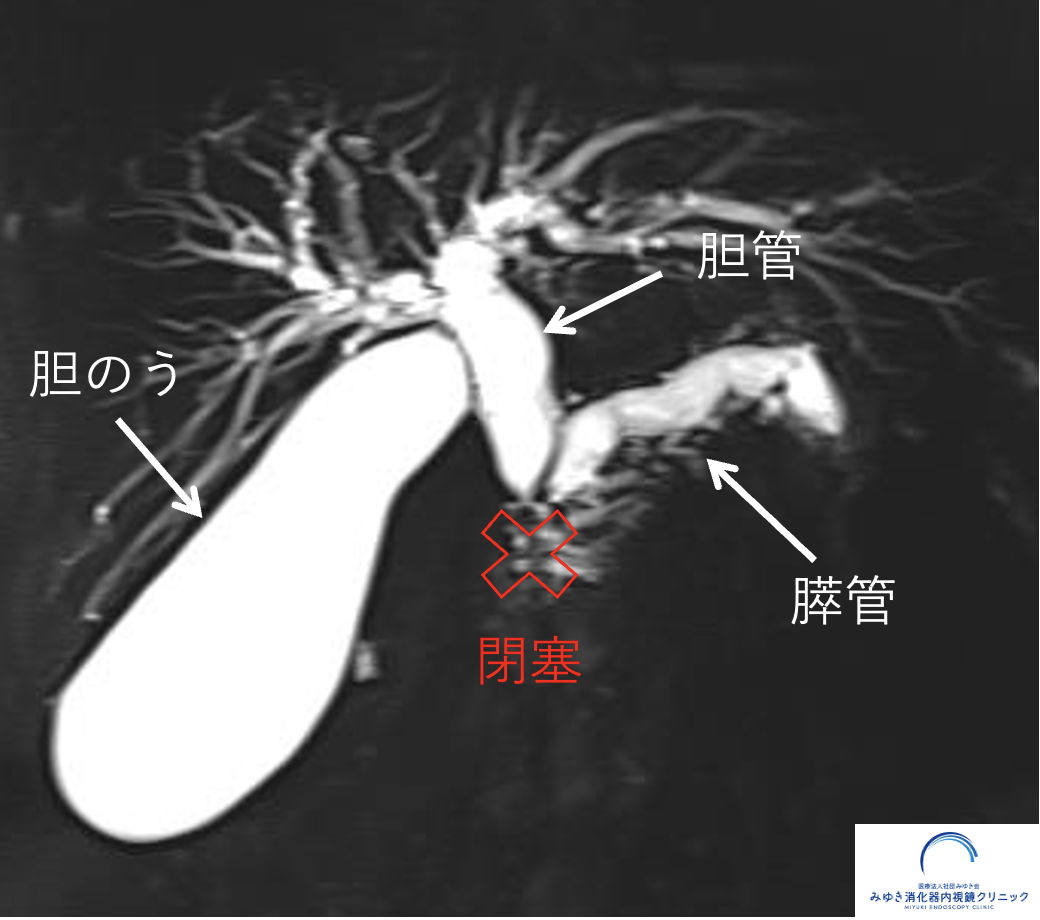

MRIと超音波内視鏡による膵がんドック